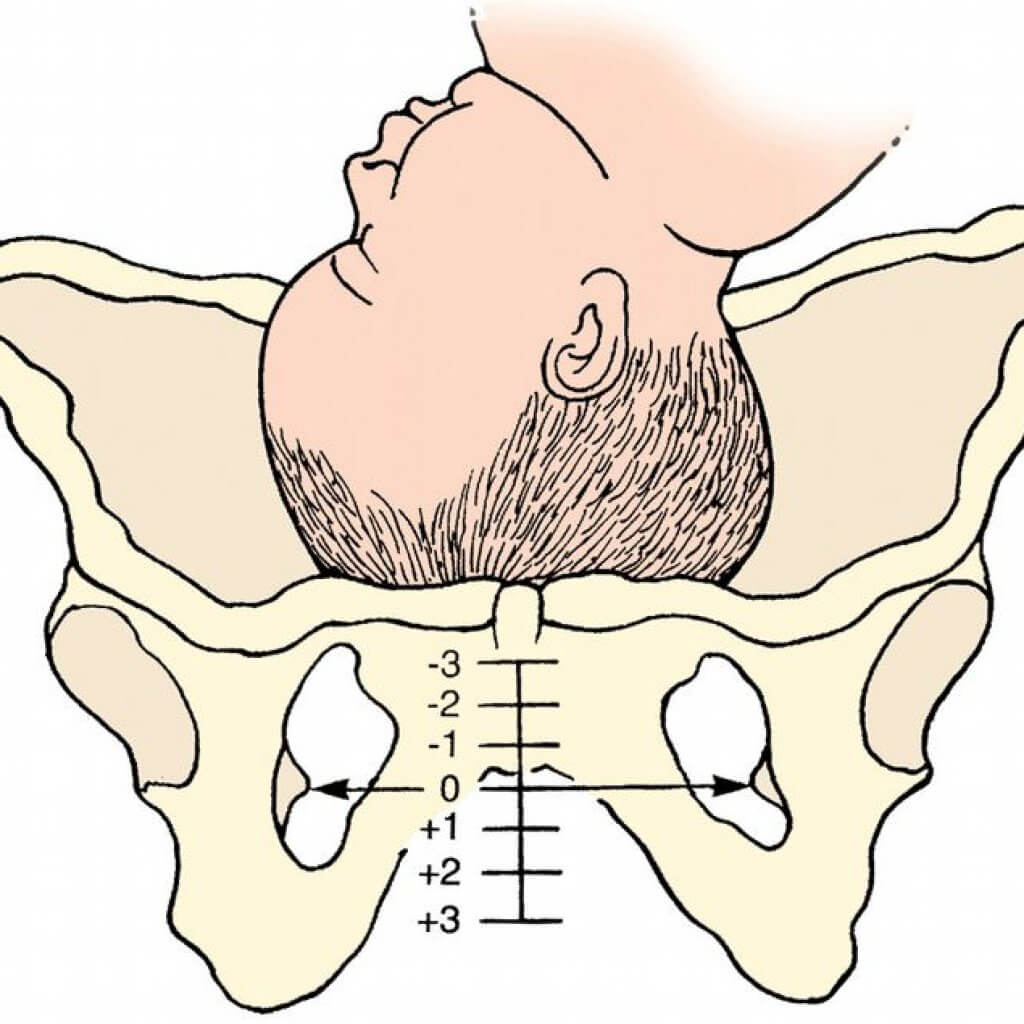

Normal 36 weeks pregnancy and ultrasound, your complete guide.

Normal 36 week baby ultrasound. – Ultrasoundfeminsider

All About 36 Weeks Pregnant – Stomach, Body, Fetus, Diet, And Development